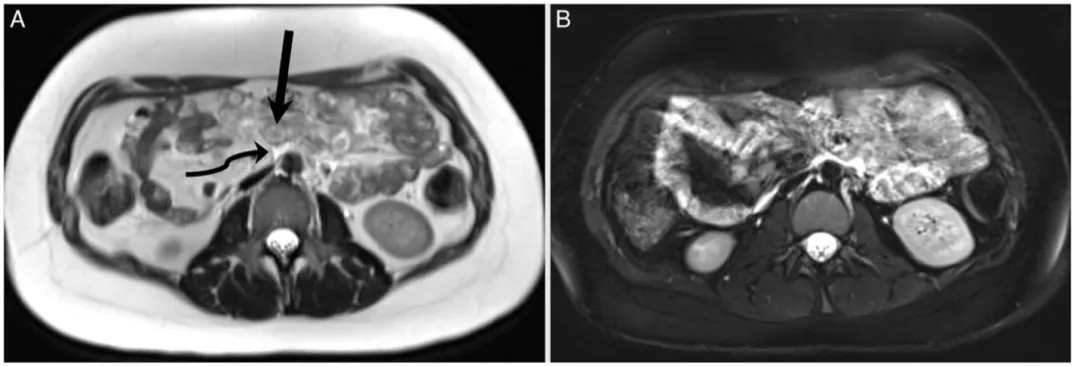

他们决定引入第三只眼——MRI。

同一天做的MRI T2加权像显示,这些“肿瘤结节”周围有着广泛的弥漫性水肿信号(图3)。

图3.患者MRI图像显示肠壁弥漫性水肿

T2高信号水肿:更倾向于炎性渗出。